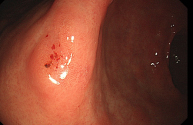

정상 위의 내시경 사진

조기위암